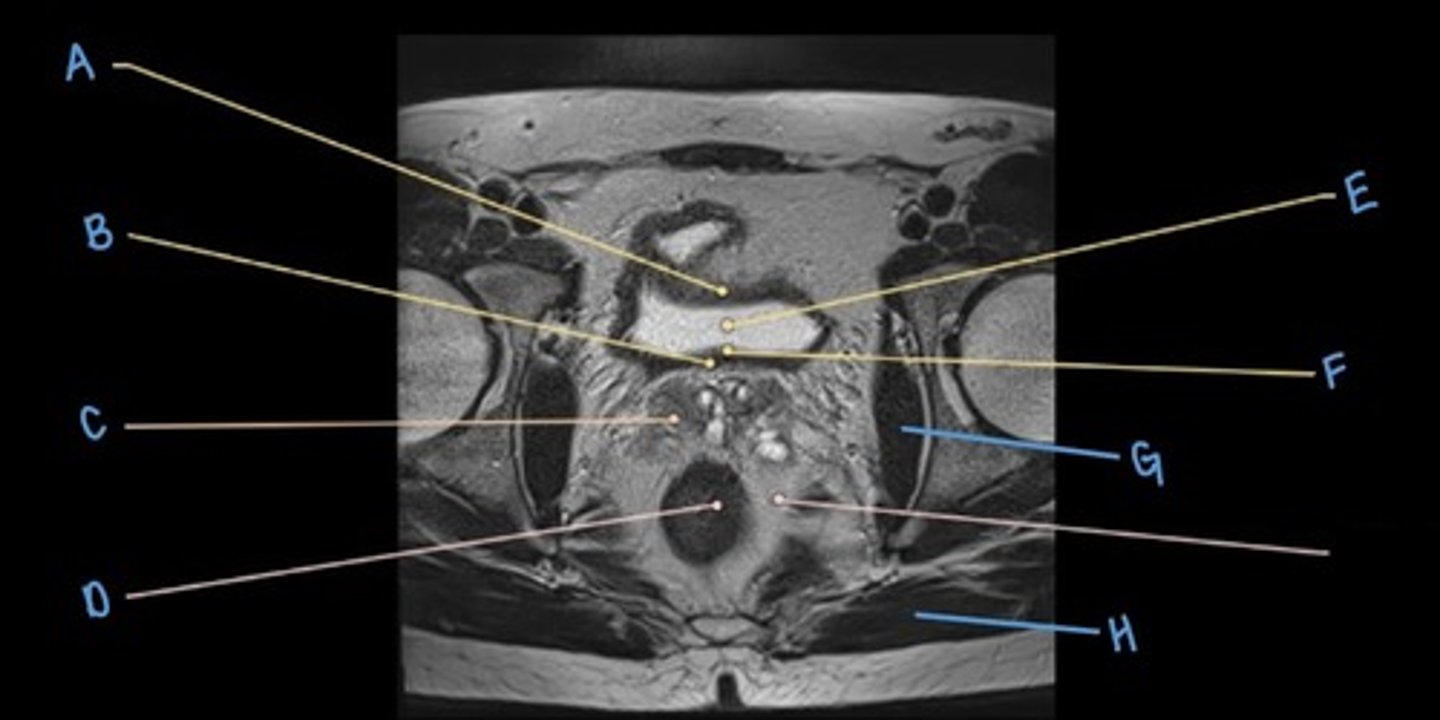

superior pubic ramus

A

rectus abdominus muscle

B

iliopsoas muscle

C

obturator internus muscle

D

rectum

E